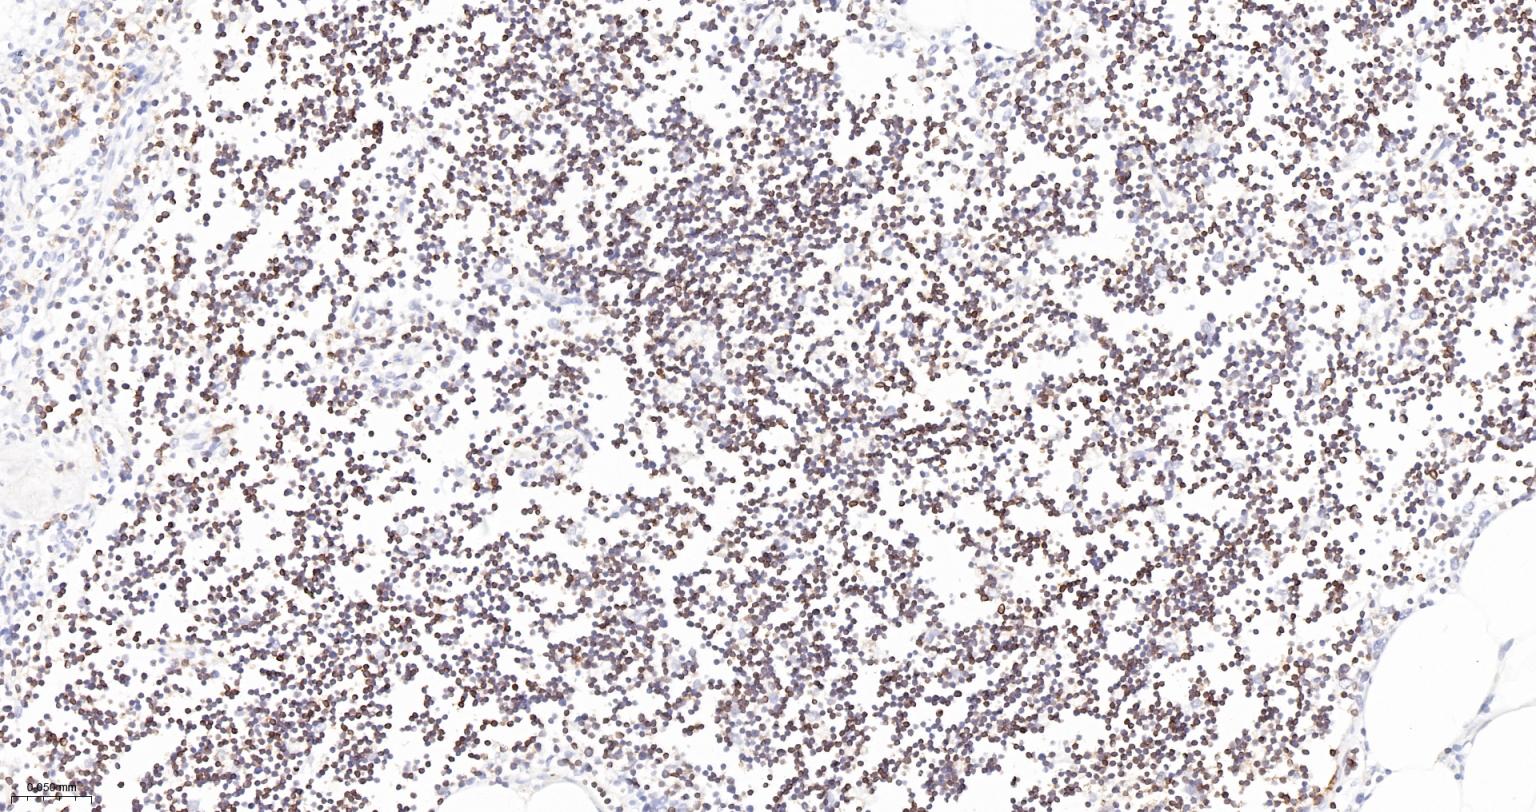

Paraformaldehyde-fixed, paraffin embedded Human Thymus; Antigen retrieval by boiling in sodium citrate buffer (pH6.0) for 15 min; The section was incubated with CD3E Monoclonal Antibody, Unconjugated (bsm-54036M) at 1:200 overnight at 4°C, followed by conjugation to the bs-40296G-HRP and DAB (C-0010) staining.